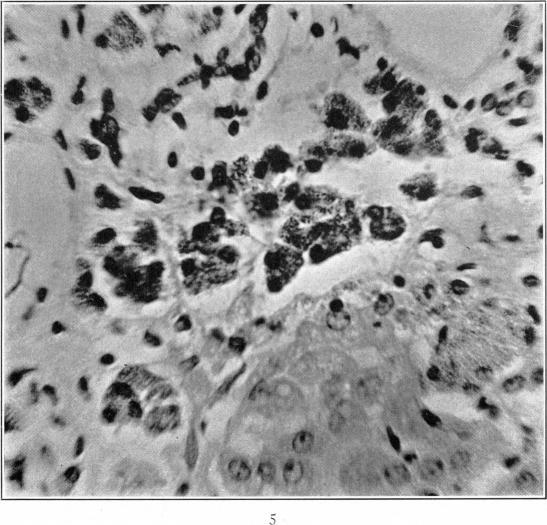

Experimental Hepatic Pigmentation and Cirrhosis: I Does Copper Poisoning Produce Pigmentation and Cirrhosis of the Liver?

Am J Pathol. 1931 Jul;7(4):327-342.5.